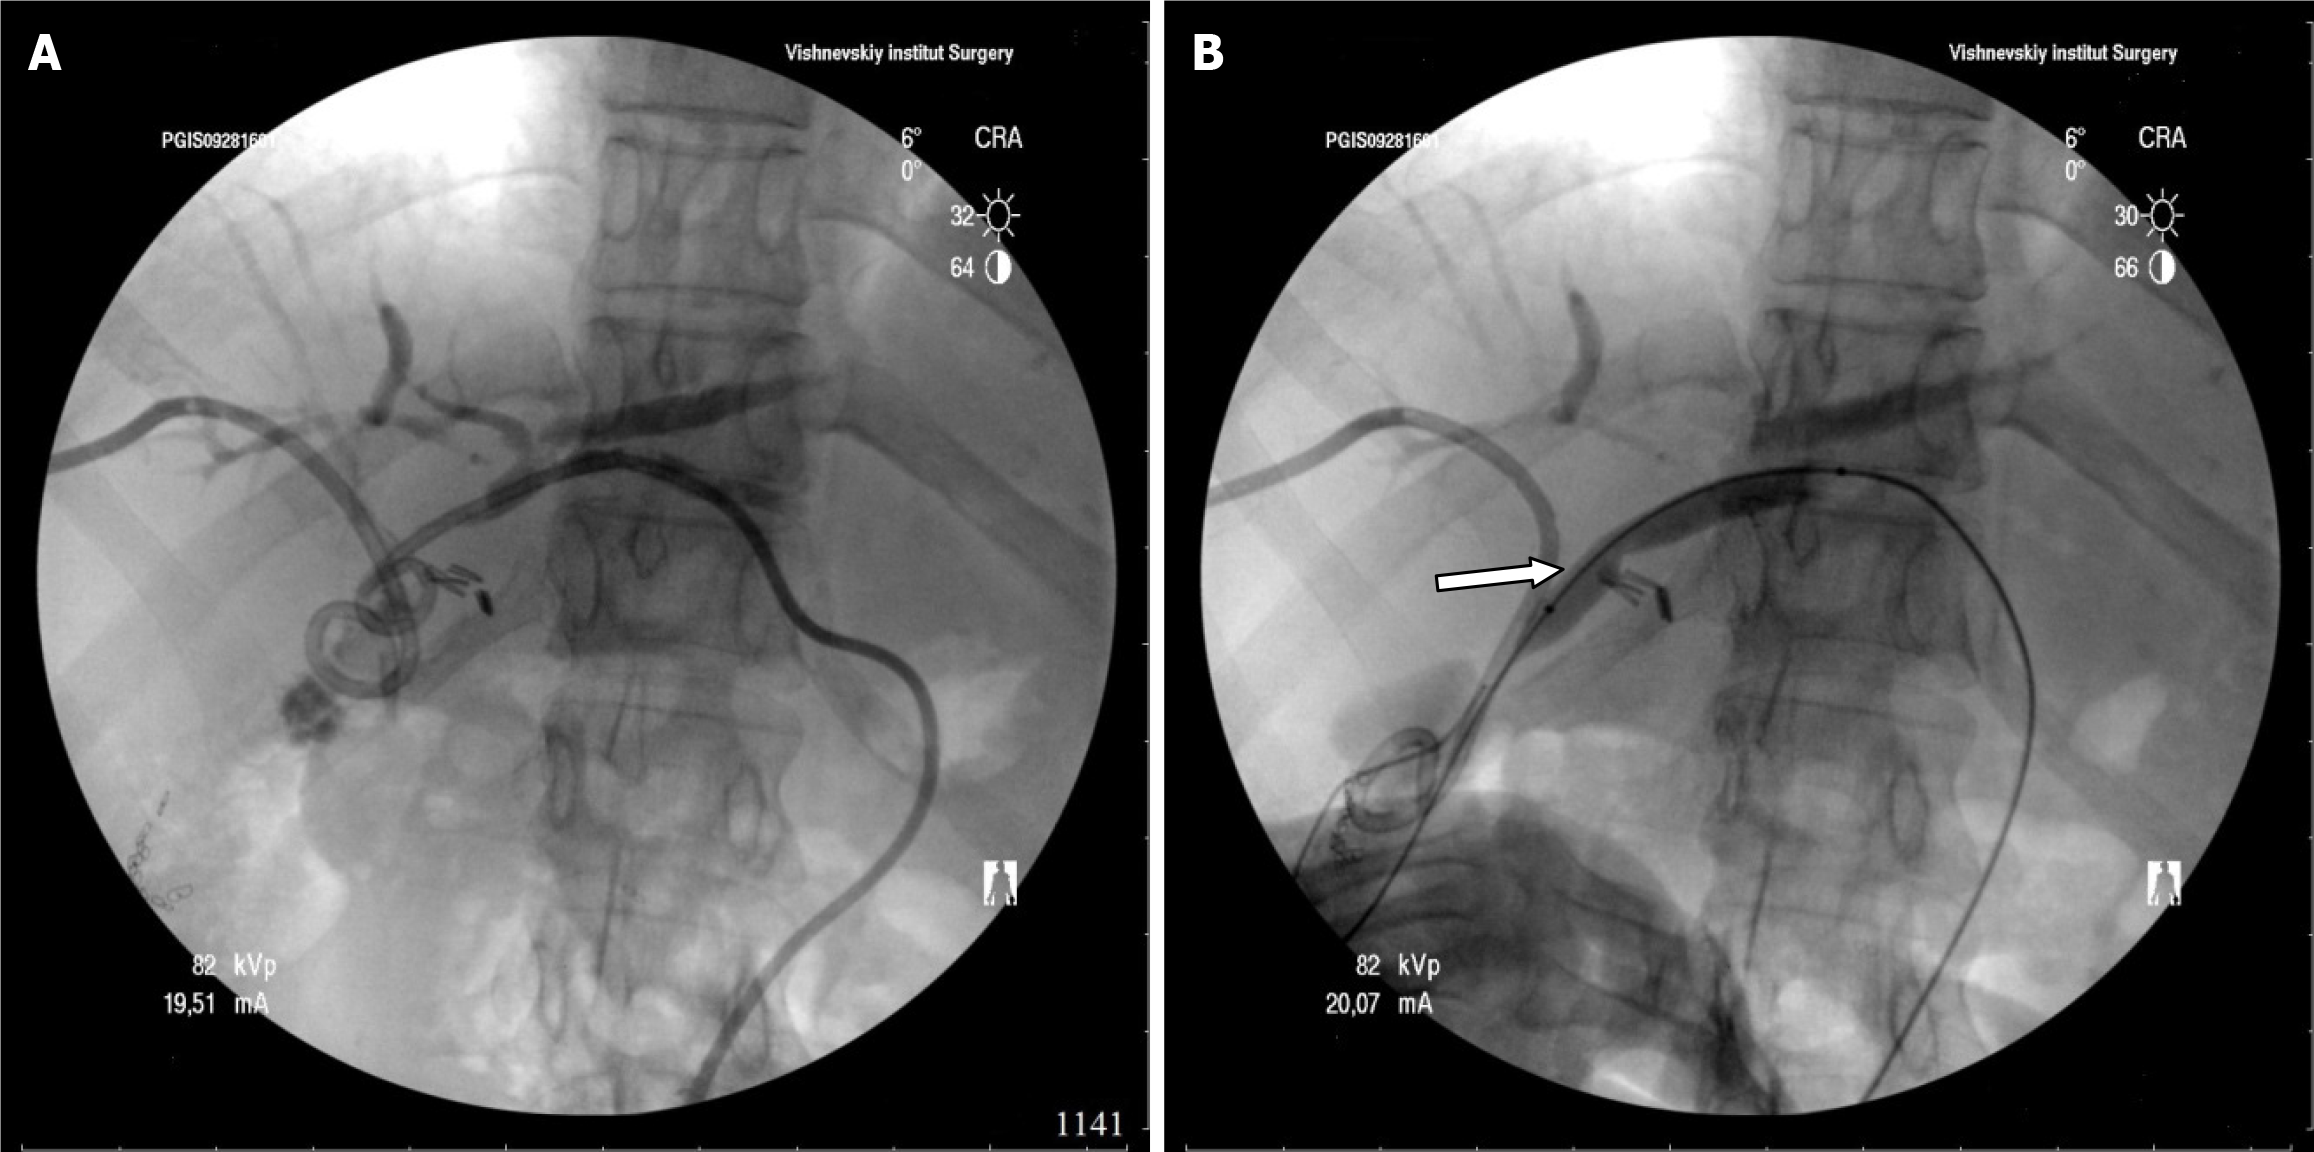

In the first phase, 111 of 193 patients (57.5%) underwent PTBD for resolution of obstructive jaundice and/or treatment of acute cholangitis. The nature of the procedures is shown in Table 1. Technical success of external-internal biliary drainage and balloon dilatation of strictures was achieved in 70 (63.1%) patients (Figure 1). The reason for failure was the presence of complete stricture of the hepaticocholedochal duct or lobular, segmental bile duct in 33 patients, complete stricture of the hepatojejunostomy in 8 patients.

Out of 70 patients who underwent PTBD was abandoned in 4 patients because of large multiple cholangiolithiasis. In one patient-because of stricture of hepaticoduodenostomy. Thus, we performed stage percutaneous transhepatic treatment in 70 patients. The duration of biliary tract drainage ranged from 3 to 50 months (median 17.4 months). The number of balloon dilatations ranged from 1 to 12, the median number was 5 procedures.